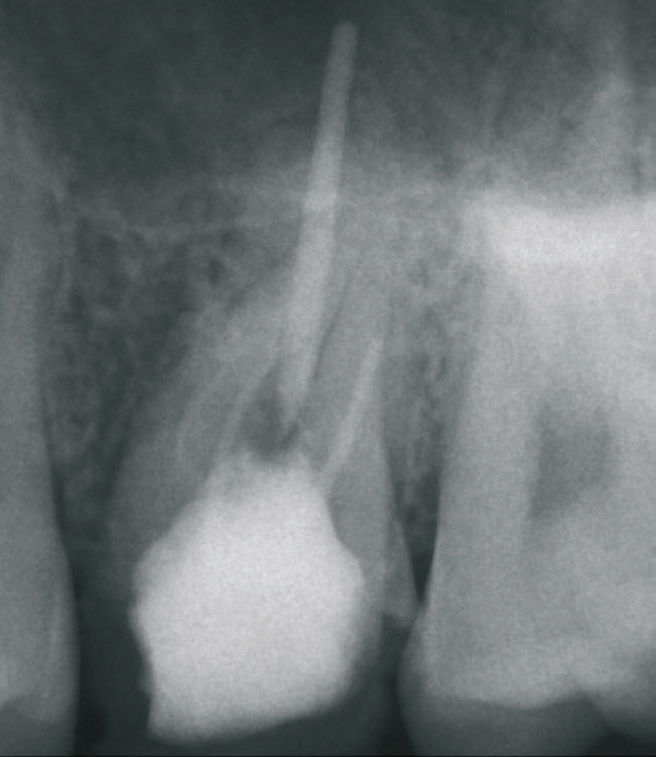

Ein 21-jähriger Patient stellte sich mit einer Perkussionsempfindlichkeit in regio 26 vor. Die klinische Untersuchung zeigte einen tiefzerstörten Zahn 26, dessen gesamte palatinale Wand tief fraktruiert war. Die Frakturgrenze verlief dabei weit unter dem palatinalen Zahnfleischrand (Abb. 1). Nach Erstellung eines Orthopantomogramms und einer radiologischen Einzelzahnbildaufnahme war eine längliche Verschattung am Apex der palatinalen Wurzel des Zahn 26 zu erkennen (Abb. 2), die den Verdacht einer überinstrumentierten Wurzelkanalaufbereitung der palatinalen Wurzel und einer Überstopfung des Füllmaterials bestätigte (Abb. 3). Nach konservierender Theapie wurde die Indikationsstellung für die Extraktion des Zahnes 26 mit einer Sofortimplantation gestellt. Der Periodontal-Screening-Index wies in allen Sextanten Grad 2 auf. Es folgte die Erstellung einer dreidimensionalen Röntgenaufnahme (Orthophos XG 3D, Dentsply Sirona, Bensheim) zur virtuellen Planung der Implantatposition. Die operative Planung erfolgte in der Planungssoftware coDiagnostiX 9.5 (dental wings, Montreal, Kanada) (Abb. 4).